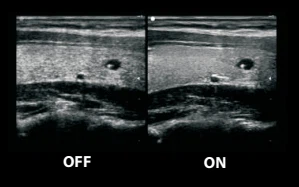

ZClear

Tехнология отслеживает специфические сигналы от краев ткани в режиме реального времени для улучшения границы и контура, одновременно отслеживая каждый пиксель для оптимизации сигнала от ткани. Эффективно устраняет шум и идеально формирует изображения границ ткани и двумерную визуализацию с улучшенным контрастом.